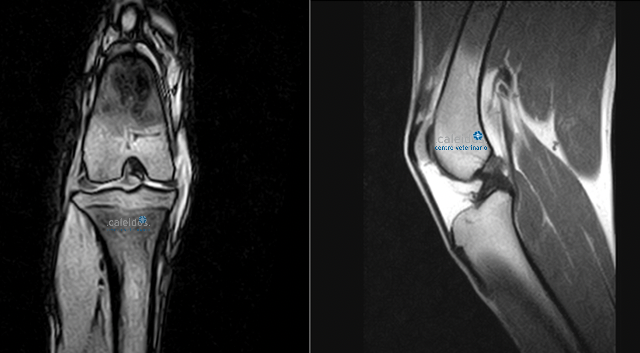

At Caleidos clinic we also do MRI of knee joints, a method that is not very widespread in the veterinary field.